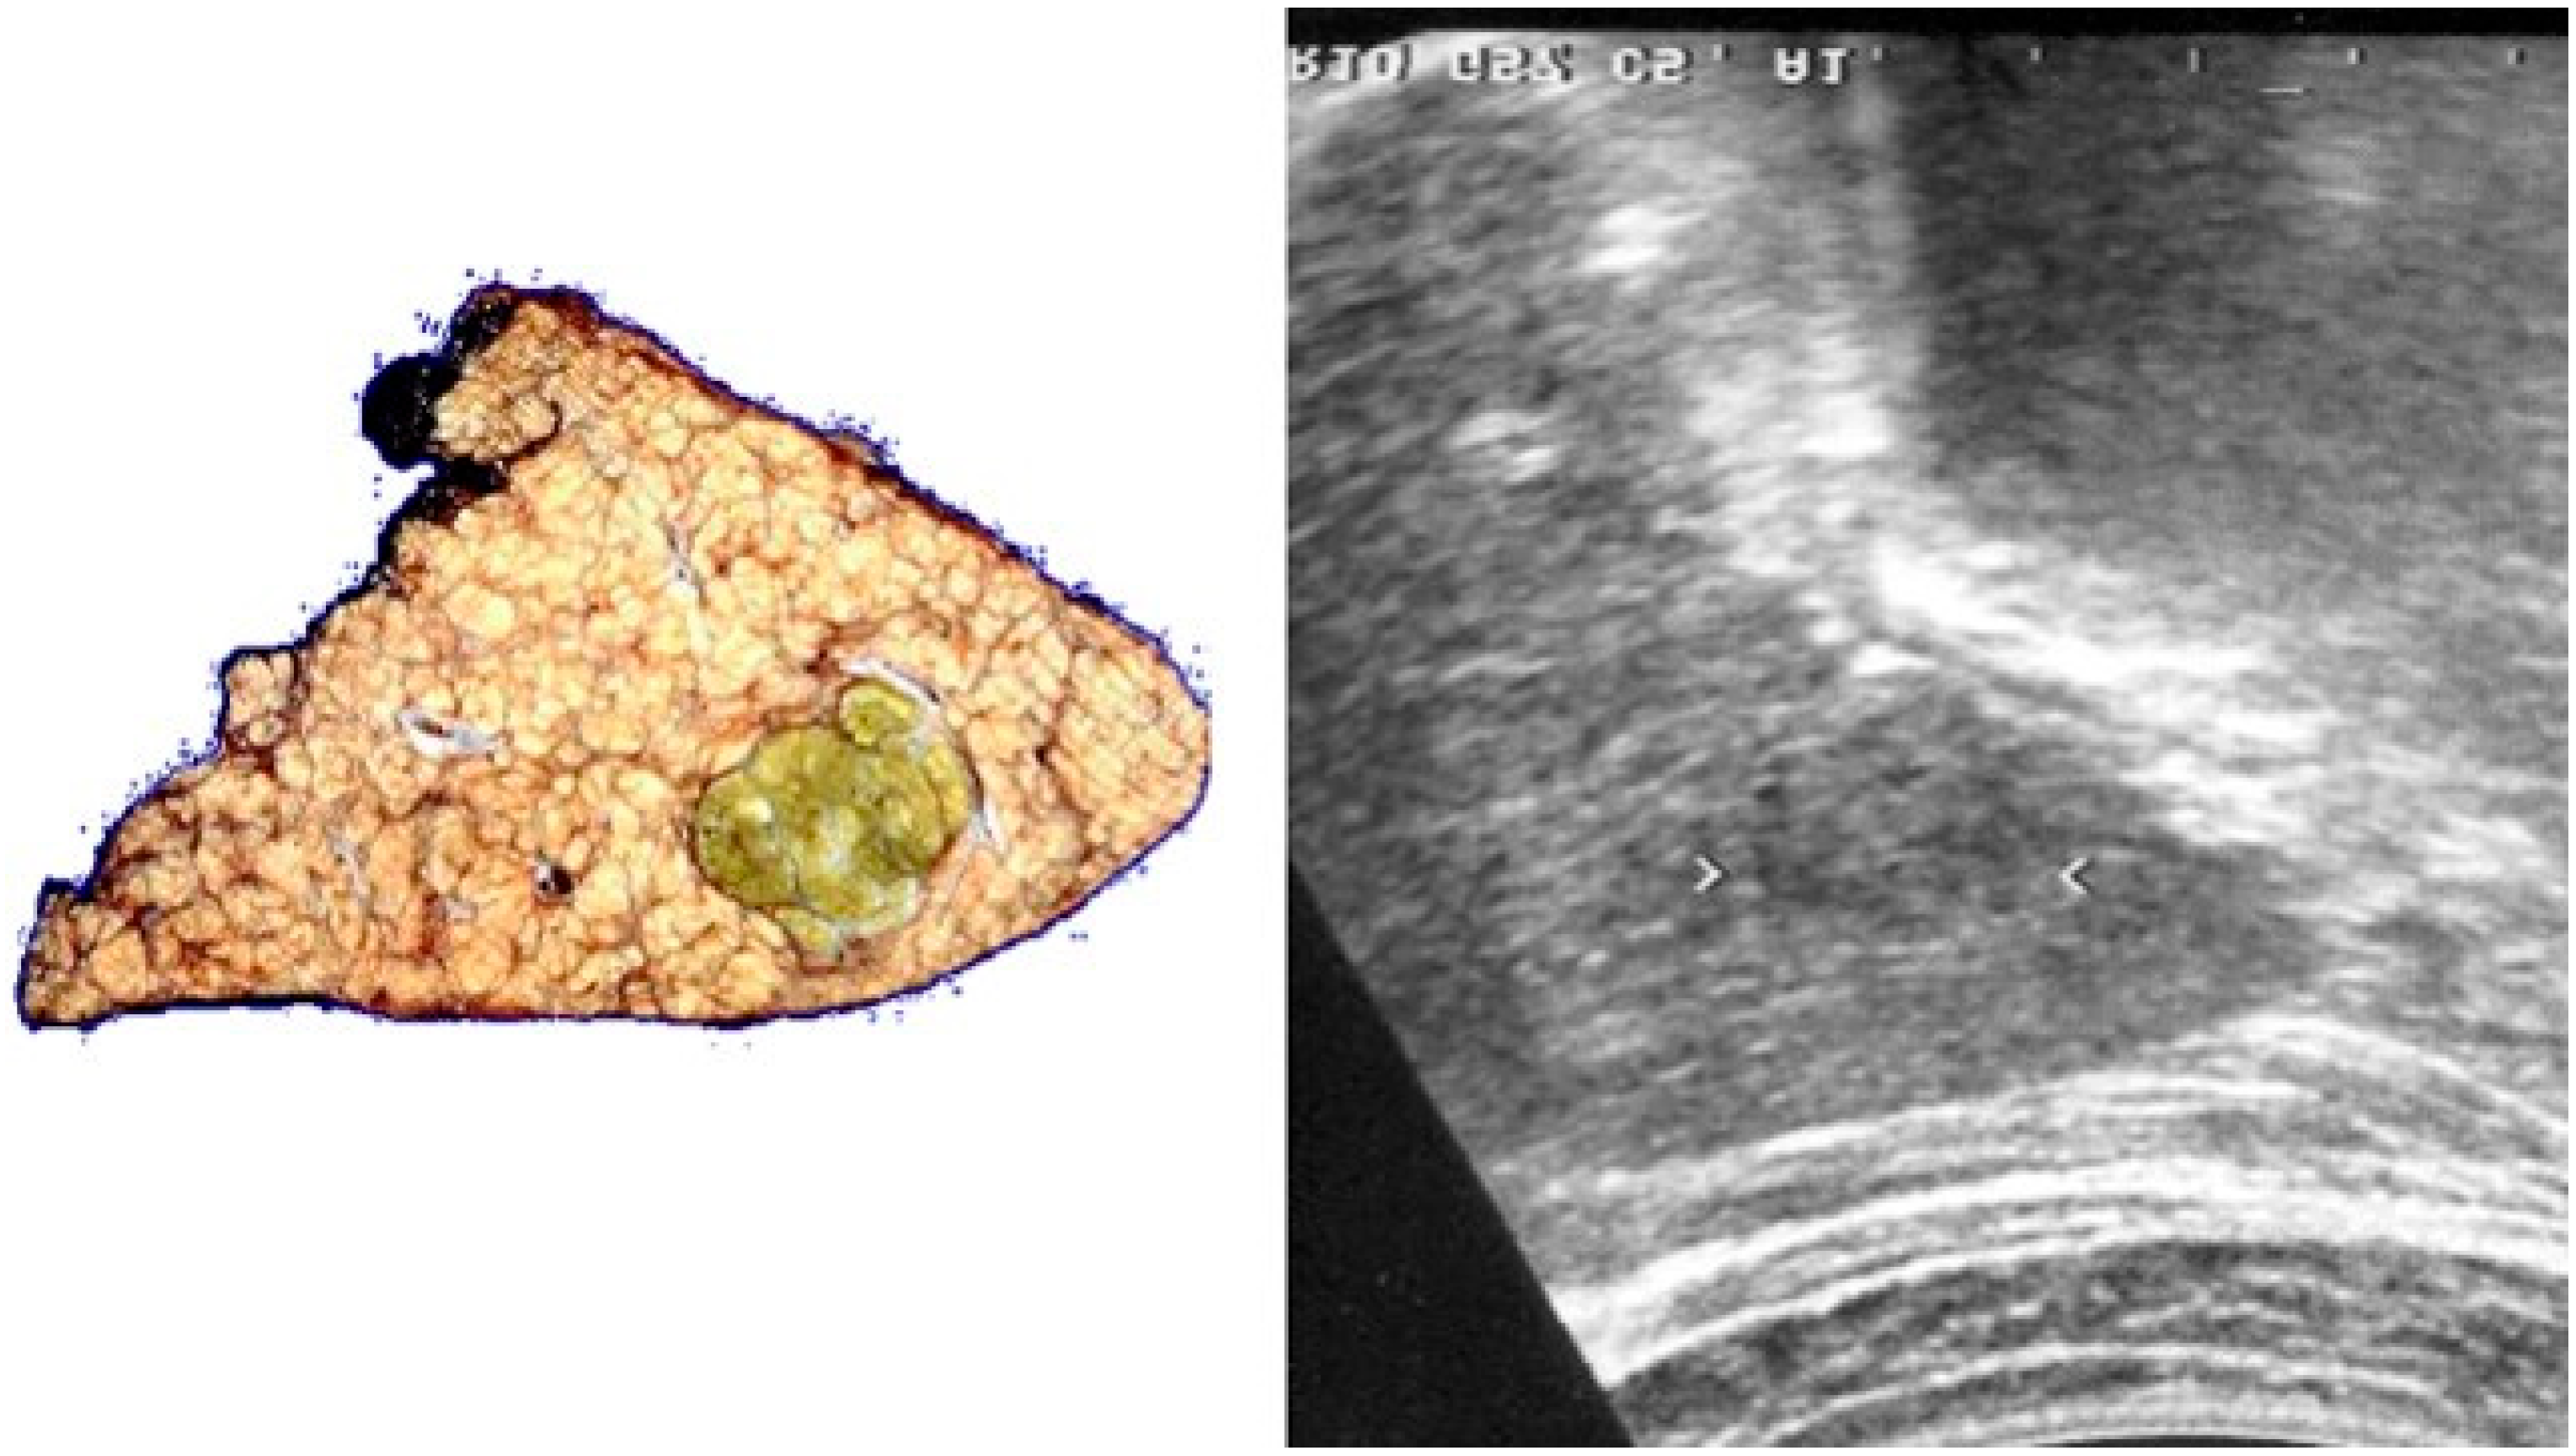

| POST-VIRAL HCC | MASLD HCC |

|---|---|

|

| |

| These characteristics would be focused more on the lack of malignancy rather than HCC. | |